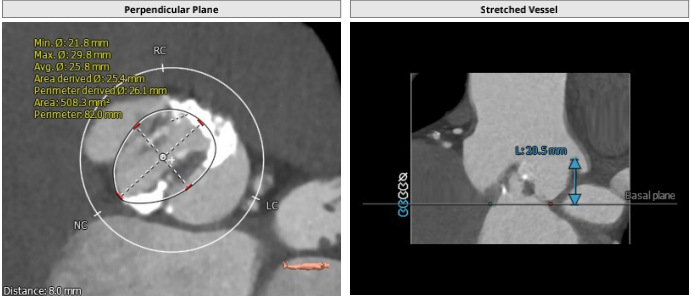

主动脉根部解剖: